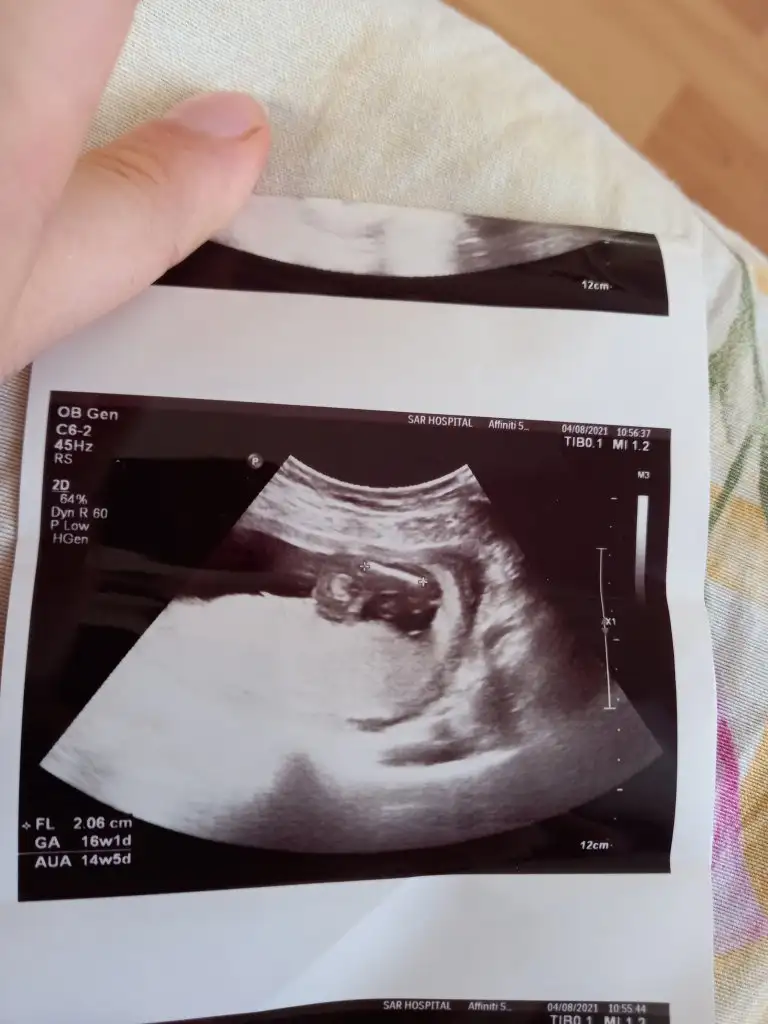

Bir de 16 haftalık ultrasona bakar mısın lütfenYüzde yüz milyon erkek besbelli canım benim oğlumun da böyleydi ultrason görüntüleri

Eki Görüntüle 2898299

Olur teşekkürlerAynen bacak arasında nohuta benzer gözüküyor erkekte bende oğlumun ultrason görüntülerini bulup atayım inşaEllah bi ara canım karşılastır